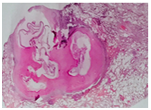

A 23 year-Old Iranian female patient presented with a six months history of fever, chest and abdominal pain, loss of appetite, weight loss, cough, night sweating and dyspnea was referred to our hospital. Physical examination revealed fever (39 centigrade), blood pressure 110/60 and coarse crackles at middle and lower area of both lungs. Abdomen was soft but a budging was seen in lower abdomen near the suprapubic region. Others organ, upper and lower extremity was normal. There was bilateral multiple nodular lesions at his chest X-ray. In hospital she takes ceftriaxone 2Gr and clindamycin 600mg twice daily. US of abdomen and pelvic was obtained and showed a cystic–solid lesion in the pelvic and in the liver. Computed tomography (CT) scan of the chest, abdomen and pelvic with IV contrast was obtained and showed multiple cavitary and solid-cystic mass lesions was showed in both lungs and the size of lesions were various in diameter. The lesions were located in the central and peripheral zone of both lungs (Figure 1). The abdomen and pelvic CT–scan showed solid-cystic mass in the pelvic and liver Radiologist finding and differential diagnosis was inflammatory lesion as Wegener granuloma, septic emboli, sarcoidosis and pulmonary metastasis from ovarian malignancy (Figure 2). Two days after admission, fever dropped and general condition of the patient becomes better. All lab date was normal except (ESR=40(0–20mm/h.CRP=22(0–5mg/L), WBC=16000). Fibroptic bronchoscopy was performed. Endobronchial lesion was not observed and bronchial lavage was obtained, Pathology examination of the bronchial lavage was normal, all other biochemical tests (CEA, ACE, RF, CA-125, hydatid tests and rheumatological tests) were normal. Laparatomy was performed ,the pelvic mass was excised and mass was opened, laminated membrane of hydatid cyst was seen, the lesion of liver was aspirated and fluid was clear, the mass was opened carefully and laminated membrane was seen (Figure 3) (Figure 4). With left mini anterolateral thoracotomy at 4 thintercostal space, chest wall was opened multiple nodules was palpable the big one was resected as wedge resection, the specimen was opened, laminated membrane was exposed (Figure 5). Chest tube was inserted and chest wall was closed in layers. Second post operative day, Albendazole was started at a dose of 10mg/kg/day for three cycle of 28days with 14days interval. Pathologist’s repot was hydatid cyst of lung in all three specimens (Figure 5). Patient was discharged in good condition 5days postoperative in the six months follow -up time there was no increased the size of both pulmonary nodules.

Figure 4 Laminated membranes of liver and ovary hydatid cyst.

Figure 5 daughter cyst of liver and ovary hydatid cyst.